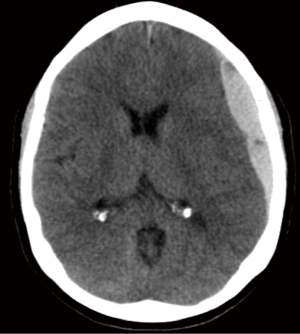

Decompressive craniectomies

Indications for DC)for TBI can plainly be described as sustained elevated ICPs not responsive to medical management (38). The patient’s injury type, clinical status, and intraoperative observations are the main determinants of surgical decision-making. By convention, decompressive craniectomies are noted as life-saving procedures to prevent further compounding secondary injures and central herniation (48). DCs are typically considered for diffuse brain injury vs. focal extra-axial or parenchymal injury. Open skull fractures, considered “dirty” may also be removed and left off for reasons other than for decompression (38). Severe TBI, by definition, with low GCS, brainstem involvement, and intraventricular involvement are associated with poor outcome with or without a DC (49-53). With such a wide array of both clinical and radiographic presentations with a high degree of patient-specific individuality, the role for DC in severe TBI is yet to be defined (Figure 6).